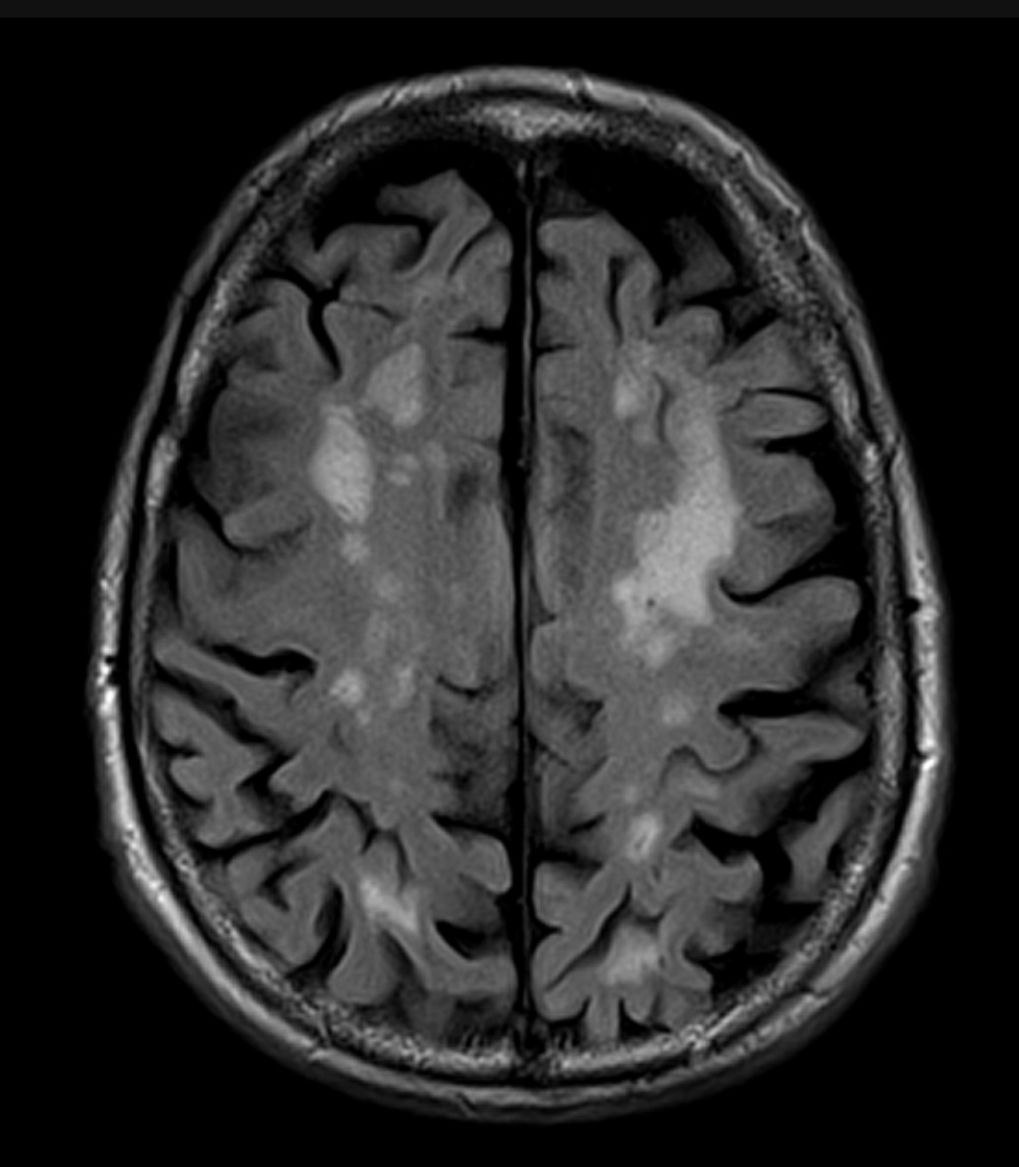

Хроническая ишемия головного мозга на МРТ.

🧠 Хроническая ишемия головного мозга — это состояние, при котором ткань головного мозга не получает достаточного количества кислорода и питательных веществ из-за недостаточного кровоснабжения. Это может произойти в результате различных факторов, основными из которых являются атеросклероз, артериальная гипертензия, диабет.

➡️ В результате в веществе головного мозга происходит постепенное замещение нормальной мозговой ткани клетками глии - появляются очаги и фокусы глиоза.

👀 По МРТ в первую очередь мы оцениваем эти изменения на T2 ВИ и импульсной последовательности FLAIR, на которых очаги глиоза имеют гиперинтенсивный МР-сигнал, по Т1 ВИ данные очаги могут быть изо-гипоинтенсивны.

Данные очаги зачастую сливаются в зоны глиоза, на фоне которых мы нередко видим лакунарные кисты - последствия лакунарных инсультов.